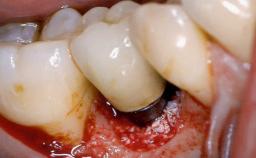

Occlusal Load—a Factor for Implant Failure?

In this case, Nicola Zitzmann describes the sudden loss of a previously well-osseointegrated implant that had been in healthy function for 5 years. The case includes recommendations for occlusion and function of implant restorations. A 74-year-old patient had received implant-fixed dental prostheses in the maxilla in 2008, and in the right mandible three years later. His tooth loss was mainly related to recurrent caries associated with hyposalivation as a potential side effect of his cholesterol-lowering medication.